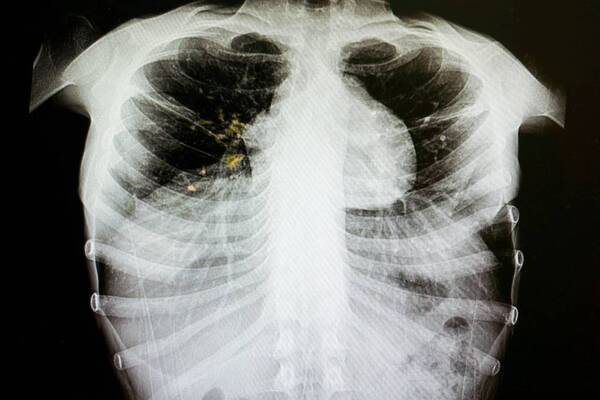

Признаки обычной простуды могут сигнализировать о серьезных болезнях с летальным исходом. Высокая температура, боль в горле, недомогание…